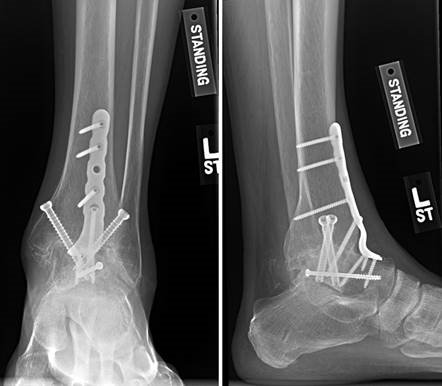

The ankle joint, an articulation between the tibial plafond, medial malleolus, lateral malleolus, and talus, is responsible for the majority of sagittal plane motion: dorsiflexion (10–23°) and plantarflexion (23–48°). Due to the trapezoidal shape of the talar dome, the mortise widens and the ankle becomes inherently more stable in dorsiflexion. The medial deltoid ligament complex acts as the main stabilizer of the ankle during stance, resisting lateral translation and valgus forces (talar tilt), while the lateral ligamentous complex acts as a primary restraint to varus forces. Proximal to this, the distal tibiofibular joint—consisting of the convex distal fibula and the concave incisura fibularis—allows the fibula to externally rotate approximately 2° during normal gait. Along with the syndesmotic ligaments, this articulation provides crucial stability against lateral talar translation.

Positioning of the fusion is the most critical step of the operation. The hallux must be positioned in 10-15 degrees of valgus, 15-20 degrees of dorsiflexion relative to the first metatarsal, and neutral rotation. Excessive dorsiflexion causes shoe impingement, while insufficient dorsiflexion leads to vaulting during gait and interphalangeal joint arthritis. Fixation is most reliably achieved using a pre-contoured dorsal locking plate combined with a lag screw crossing the fusion interface.

| Nonunion (Lapidus/MTP) | 3 - 10% | Inadequate cartilage resection; Poor fixation construct; Patient non-compliance; Smoking. | Revision arthrodesis with structural bone grafting and robust locking plate fixation. |

| Hardware Irritation | 10 - 20% | Prominent screw heads or dorsal plates under thin soft-tissue envelope. | Symptomatic hardware removal after radiographic confirmation of complete union. |